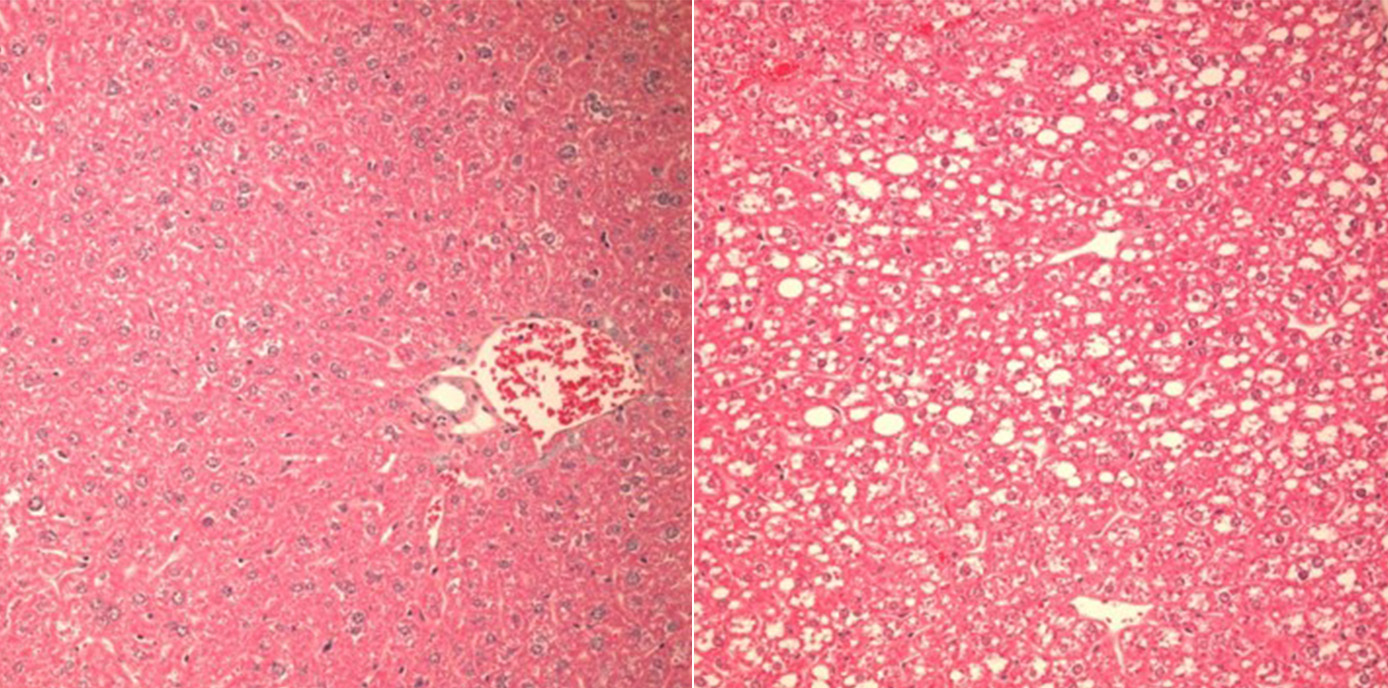

Auch wenn man noch wenig über Auslöser und Art der Caspase-2-Aktivierung in der verfettenden Leber weiß, konnten die ForscherInnen nun zeigen, dass der Verlust des PIDDosoms bei Fruktose-reicher Diät vor der Zerstörung von Leberzellen, Entzündung und Gewichtszunahme schützt. „In unseren Mausmodellen gelang es, den Einfluss des PIDDosoms auf den Lipid-Stoffwechsel und die Entwicklung hin zur Leberentzündung klar darzustellen: War Caspase-2 ausgeschaltet, entwickelten Mäuse trotz Fruktose-haltiger und Fettsäure-reicher Diät keine Leberschädigung, da die Enzyme, die sonst zur Leberverfettung führen, nicht aktiviert wurden“, beschreibt Villunger die zentrale Erkenntnis.

(29.09.2022, Text: D. Heidegger, Bild: V. Sladky )